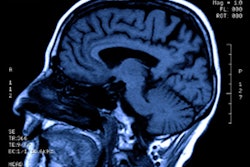

MRI shows eight particular neurologic findings in patients with severe COVID-19, according to a study published June 16 in Radiology.

The study included 37 patients evaluated between March 23 and April 27 at 16 hospitals who had the following clinical findings: positive nasal or lower respiratory tract reverse transcription polymerase chain reaction (RT-PCR) assays, severe COVID-19 infection that required hospitalization and oxygen, neurologic manifestations, and abnormal brain MRI scans.

The group outlined eight neurologic patterns in patients with severe COVID-19 and abnormal MR images:

- Signal abnormalities in the medial temporal lobe (43%)

- Nonconfluent multifocal white matter hyperintense lesions on fluid-attenuated inversion recovery (FLAIR) and diffusion MRI sequences, with variable enhancement and associated hemorrhagic lesions (30%)

- Extensive white-matter microhemorrhages (24%)

- Extensive and confluent supratentorial white-matter FLAIR hyperintensities (11%)

- FLAIR and diffusion ovoid hyperintense lesions located in the central splenium of the corpus callosum (5%)

- Nonconfluent multifocal white matter hyperintense lesions on FLAIR/diffusion, with variable enhancement (5%)

- Acute necrotizing encephalopathy (5%)

- FLAIR or diffusion hyperintense lesions involving both middle cerebellar peduncles (5%)